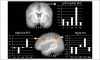

Craving of unhealthy food is a common target of self-regulation, but the neural systems underlying this process are understudied. In this study, participants used cognitive reappraisal to regulate their desire to consume idiosyncratically craved or not craved energy-dense foods, and neural activity during regulation was compared with each other and with the activity during passive viewing of energy-dense foods. Regulation of both food types elicited activation in classic top-down self-regulation regions including the dorsolateral prefrontal, inferior frontal, and dorsal anterior cingulate cortices. This main effect of regulation was qualified by an interaction, such that activation in these regions was significantly greater during reappraisal of craved (versus not craved) foods and several regions, including the dorsolateral prefrontal, inferior frontal, medial frontal, and dorsal anterior cingulate cortices, were uniquely active during regulation of personally craved foods. Body mass index significantly negatively correlated with regulation-related activation in the right dorsolateral PFC, thalamus, and bilateral dorsal ACC and with activity in nucleus accumbens during passive viewing of craved (vs. neutral, low-energy density) foods. These results suggest that several of the brain regions involved in the self-regulation of food craving are similar to other kinds of affective self-regulation and that others are sensitive to the self-relevance of the regulation target.